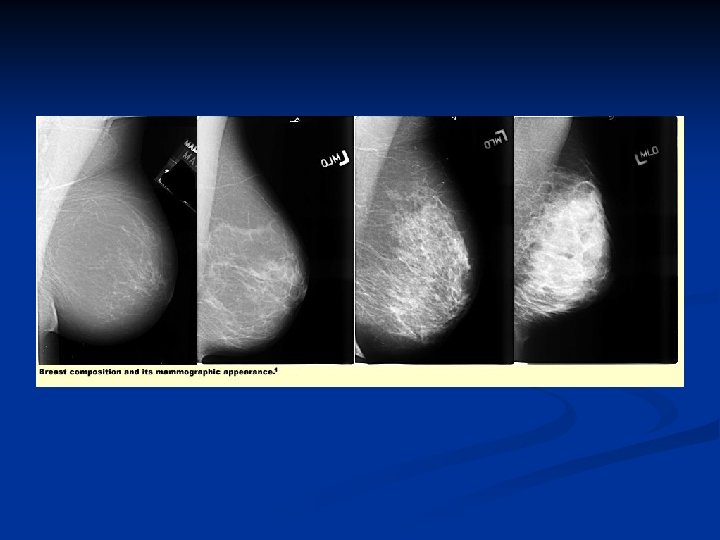

Beoordeling mammogram Mamma Densiteit De mamma bestaat vrijwel volledig uit vetweefsel (<25% klierweefsel) n Er zijn verspreid velden fibroglandulair weefsel (25 -50%) n Heterogeen verspreide velden fibroglandulair weefsel (51 -75%) n Zeer dens klierweefsel (> 75% glandular) n